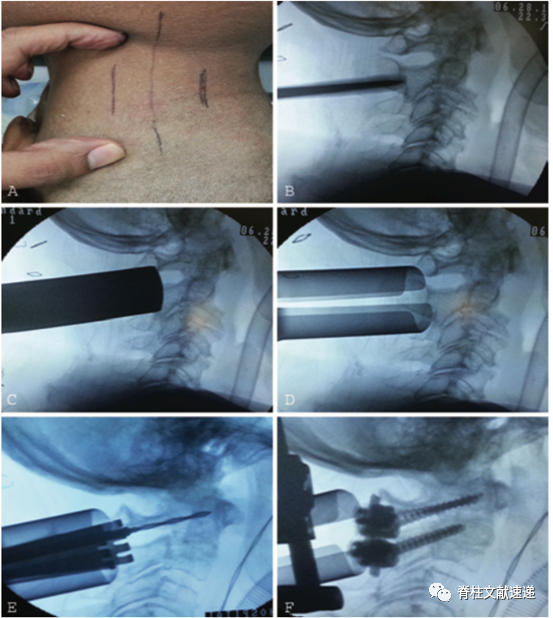

作者先在4具新鲜冰冻尸体进行模拟,然后将这一技术应用于5例患者,主要手术步骤如下。

1)颈后中线旁开2.5cm做纵行2.5cm皮肤切口。钝性分离软组织。

2)放置初级扩张通道在C2关节面最高点。逐级扩张,然后置入可扩张工作通道。

3)将工作通道向上倾斜,显露C1后弓、C2椎板和峡部,C1/2侧块间隙,使用明胶海绵和双极电凝止血,必要时牺牲C2神经根。

4)处理C1/2侧块间隙并植骨,然后按照标准技术置入C1侧块螺钉和C2椎弓根螺钉。在置入C2螺钉时,工作通道需要较大头倾角。

5)安装连接棒。

上图:(a)显示颈部皮肤标记和皮肤的伸展性,术中透视图像,显示最初扩张通道在C-2关节面(b),逐级扩张(C),放置可扩张工作通道(d),在C-1侧块用手钻做钉道(e)和最终内固定情况(f)。